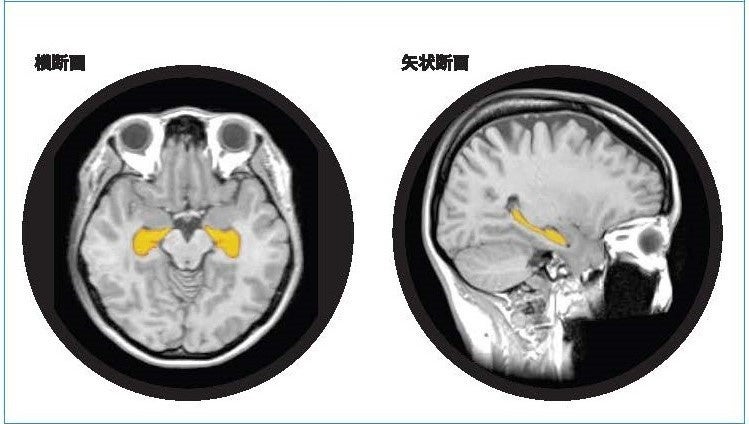

「BrainSuite®」は、東北大学加齢医学研究所による脳医学研究の成果に基づき、頭部MR画像のAI解析技術等を利用することで海馬の体積や萎縮程度を測定・評価します。同性・同世代と比較した脳の健康状態を可視化するとともに、生活習慣の改善にむけてアドバイスを提供し、行動変容を促します

「BrainSuite®」は、頭部MR画像のAI解析技術等を利用することで海馬の体積や萎縮程度を測定・評価し、同性・同世代と比較した脳の健康状態を可視化します。受検者にはBrainSuite®専用会員ページ「MyPage」が用意され、脳の健康維持・改善方法についてアドバイスを提供します。20代から80代の幅広い年齢層を対象に、「生涯健康脳」の実現を最新の脳医学の観点からサポートする検査サービスです。

アルツハイマー型認知症は、顕著な脳萎縮を特徴としおり、脳の中でも海馬の萎縮は、20・30代から始まり、生活習慣要因によっては加齢性変化以上に萎縮が加速します。予防として健康なうちより生活習慣の改善をスタートすることがとても大切です。